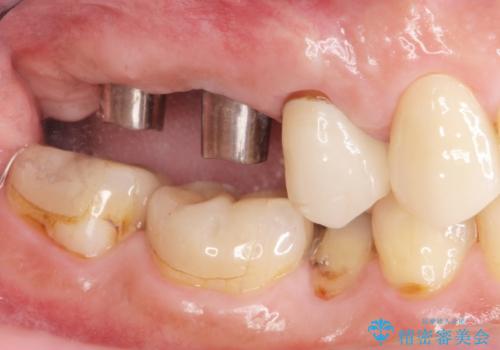

- 歯を抜いたまま放置してしまい、「やはりしっかりと噛めるような状態にしてほしい」とインプラント治療を希望され来院されました。

人工歯根であるインプラントを埋入することで奥歯でまたしっかりと噛める咬合機能を回復します。

- 88万円(インプラント×2・仮歯×2・チタンカスタムアバットメント×2・ジルコニアクラウン×2)費用は治療当時の料金となります